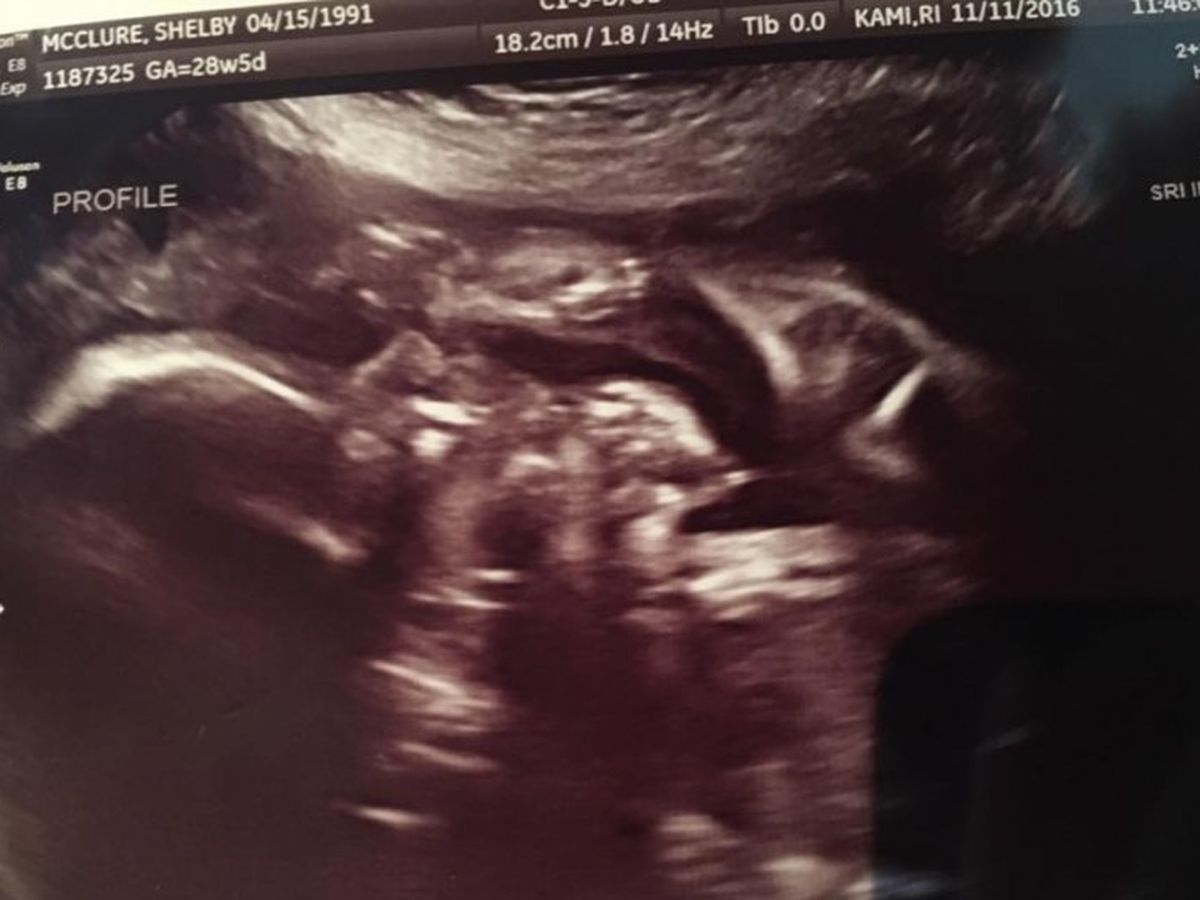

We came out pregnant with our second baby in May of 2016. Everything seemed to be going smooth and great except...bad morning sickness. You know...normal pregnancy stuff. In August I was put on bedrest...because Dr thought my placenta had detached from uterus wall a bit, but it healed perfectly after going for a check up a week and half later. Sept 9th was the big day. We were going to find out if baby McClure #2 was a boy or girl...also anatomy scan. We were excited. Little did we know...our world would come crashing down quick. They couldn't get a clear picture. The ultra sound tech's face got serious and straight all of a sudden. I knew something wasn't right. They also told us that our baby was a boy. When our dr talked to us...she told us baby's heart wasn't developing like it should and there was very little amniotic fluid and that things didn't look good. Our doctor recommneded to do the genetic blood test which it all came back negative....also it showed our baby was a GIRL. I had to ask because I knew that the ultra sound techs couldnt see a clear picture. We were sent to a specialist...which they found no kindneys (the reason for very little amniotic fluid) also..no stomach..no bladder..and she has hypoplastic left heart syndrome. Also possibly...cleft lip and club foot. We were told it was a lethal pregnancy...she could possibly be still born, go into preterm labor, or even if she made it full term...she wouldn't be able to survive outside of me. We had the option to terminate. But that wasn't an option for us at all. We believe in miracles. And if there is even a little chance for her to live...we will give her that chance.

We are currently 28 weeks pregnant. That means...12 weeks or less. And she's still moving strong. But as time gets closer....anything can happen. We aren't the family that likes to ask for help. Especially financially help from other people. We don't know what will happen. Whether it be...plan a funeral...or if God will reveal himself and put his miraculous healing hands on our sweet girl. But we know she will have health issues possibly and that would call for some medical expenses. We have a sweet boy already (Isaiah) who's 18 months. And when the time comes...sean will take off work, depending on what's going on...we won't know how long. So any donations that will help with medical expenses, our bills, needs for Isaiah, and hopefully not but funeral expenses. If you can't donate anything...prayers are greatly appreciated. Power of prayers goes a long ways.